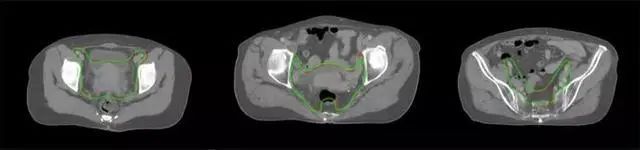

放射治療,簡稱放療,是治療腫瘤主要手段之一,利用放射線破壞照射區(qū)(靶區(qū))的細(xì)胞,使腫瘤細(xì)胞停止分裂直至死亡,醫(yī)生通常把放射治療形象的比喻為“打靶”,放療前精準(zhǔn)勾畫腫瘤靶區(qū)范圍是腫瘤放射治療的關(guān)鍵步驟。傳統(tǒng)的靶區(qū)勾畫醫(yī)生會根據(jù)患者多張CT、MRI影像片憑借經(jīng)驗(yàn)進(jìn)行,比較耗時(shí),治療的病人數(shù)量也有限,且靶區(qū)勾畫缺少行業(yè)統(tǒng)一的規(guī)范和標(biāo)準(zhǔn),無法達(dá)到同質(zhì)化,勾畫精確度不理想。

技術(shù)原理

基于深度學(xué)習(xí)人工智能的放療靶區(qū)智能勾畫技術(shù)和自動(dòng)計(jì)劃技術(shù),基于全面的市場調(diào)研和臨床專業(yè)意見,采用獨(dú)創(chuàng)的基于小樣本量的人工智能算法,實(shí)現(xiàn)放療靶區(qū)和危及器官的快速全自動(dòng)勾畫。

產(chǎn)品優(yōu)勢

縮短至幾分鐘內(nèi)便可完成,大幅提升了放療效率,且人工智能平臺完成的靶區(qū)勾畫可基本滿足臨床醫(yī)生需求,專家只需審核時(shí)細(xì)微調(diào)整,可顯著提高靶區(qū)勾畫的規(guī)范化及精準(zhǔn)度,讓放療智能化,標(biāo)準(zhǔn)化??筛采w食管癌、鼻咽癌、直腸癌、宮頸癌、肺癌等多種病種。